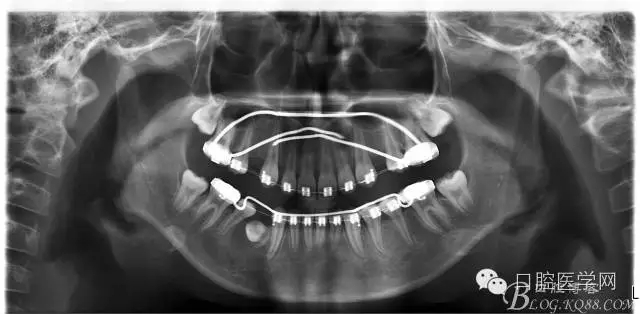

術(shù)后一個月 三個月 五個月 八個月 拔除第一雙尖牙后 曲斷片:

3:上下頜利用拔牙間隙解除擁擠并內(nèi)收上下前牙,改善唇側(cè)貌。

4:導(dǎo)下頜向前改善頜面?zhèn)让病?/p>

5:上頜TPA+NanceArch強(qiáng)支抗.

6:下頜囊腫開窗引流,雙側(cè)第一恒磨牙舌桿保持牙位。擇期拔除第一前磨牙。